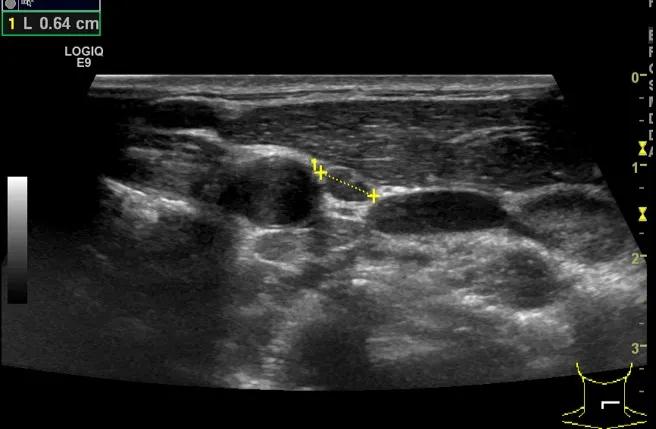

第二例是食管癌患者,术后半年余锁骨上固定淋巴结可触及肿大,疼痛非常明显,系统治疗后无缓解,患者希望通过局部处理缓解症状。造影显示强化信号明显,结节部分区域坏死,故主要针对强化区域从后向前的逐层的消融,皮下进行液体隔离减少烫伤。热消融后影像显示血流增强消失,弹性、硬度增高,一个月后复查显示充盈缺损,完全消融,疗效远超预期。

(病例2图例)